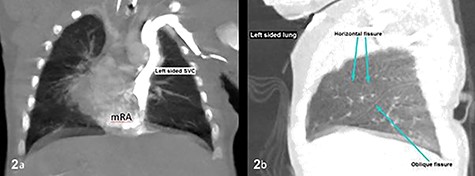

CT thorax confirmed atrial situs inversus whereby there was single left-sided SVC draining into the left-sided mRA as shown on coronal plane (a) and trilobed left lung as shown on sagittal plane in lung window (b). The pulmonary veins drain into the right-sided mLA (image not shown). Inferior vena cava was poorly demonstrable. SVC, superior vena cava; mRA, morphologic right atrium; mLA, morphologic left atrium.